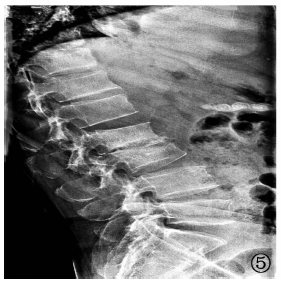

| 图5 病例3,男性,57岁。2019年3月24日,于陕西省结核病防治院腰椎摄侧位片,腰2~3椎体前缘骨质破坏,椎间隙狭窄 |